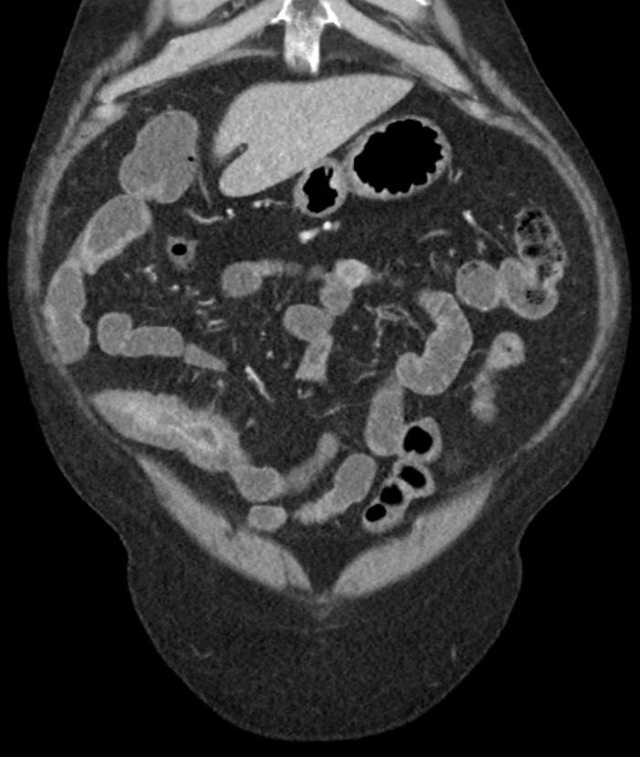

克罗恩病是一种慢性炎症性肠道疾病,会给日常饮食带来很多限制和挑战。我深刻体会到了饮食对疾病的影响,学会了慢慢调整自己的饮食习惯,寻找适合自己的饮食之道。